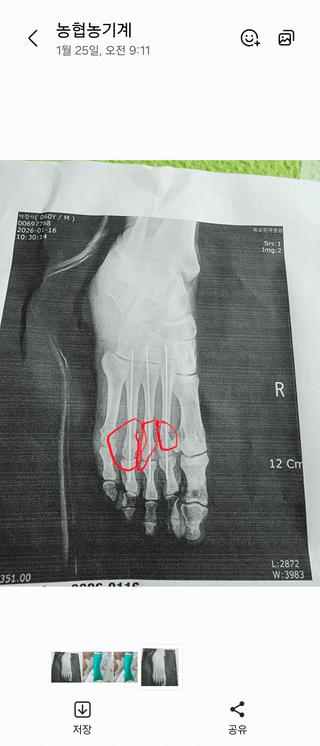

오른발중저골고절로작업불가

박정석님의 기타작물 · 영농일지 작성글 사진